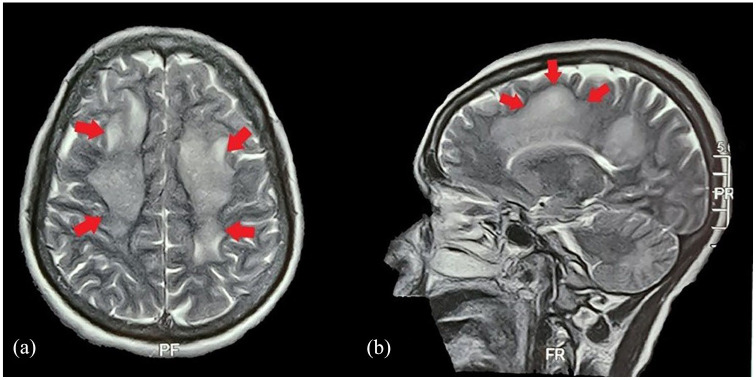

Dengue virus infection is a significant public health concern, particularly in endemic areas. This case report highlights the difficulties in diagnosing expanded dengue syndrome (EDS) in a dengue-endemic region. This case report emphasizes keeping high suspicion of index for (EDS) among patients presenting with fever and neurological manifestations particularly in regions where dengue is endemic. The atypical neurological symptoms and inconclusive initial investigations underscore the diagnostic challenges associated with (EDS). Prompt recognition and appropriate laboratory testing, such as detecting dengue NS1 antigen, can aid in accurate diagnosis and subsequent management of patients with this condition. Increased awareness among healthcare providers in endemic regions is crucial for timely identification and intervention in case of dengue-associated neurological complications. Therefore, a multidisciplinary approach is required for time-effective management.